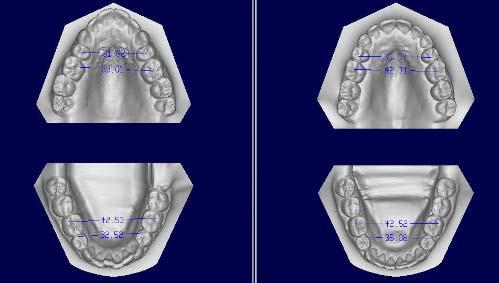

The expansion in the premaxilla can be very substantial as shown in Figures 5 and 7. Reshaping of the mandible seems to occur within the alveolar bone.

Figure 8 demonstrates the reshaping of a mandibular arch and the realignment of the teeth from start to finish.